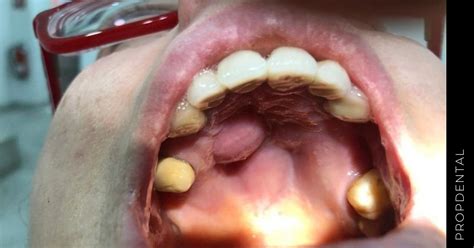

Tener un bulto en el paladar ocasiona molestias, malestar y cierta incertidumbre. Un bulto en el paladar es una protuberancia o masa que aparece en la parte superior de la boca. Estos bultos pueden tener distintos tamaños, formas y consistencia diferente, y pueden ser tanto blandos como duros si los presionamos.

En función del lugar en el que esté ubicado el bulto, de su color, de su textura y de su forma, entre otras cuestiones, podremos hablar de un tipo de problema u otro.

- Torus Palatino: Si notas un bulto duro en el centro del paladar, es muy posible que se trate de un torus palatino. El torus es básicamente un crecimiento excesivo de hueso en el paladar duro. Suele aparecer en la línea media del paladar y tiene una consistencia ósea (firme al tacto). No duele ni crece rápidamente, más bien se desarrolla lentamente a lo largo de los años. Mucha gente convive con un torus palatino sin darse cuenta, ya que suele ser asintomático y benigno. De hecho, se considera una variante anatómica normal en un porcentaje de la población. El torus palatino es una afección poco frecuente, que se explica por la formación de un bulto de hueso en el paladar. La genética suele estar detrás de este tipo de afecciones. Es una anomalía de tipo genético que produce el crecimiento de un bulto benigno que se forma en el paladar y no presenta síntomas durante su aparición. Esta alteración suele afectar más a mujeres que a hombres y sus causas son principalmente hereditarias.

- Mucocele: Un mucocele es un tipo de quiste benigno lleno de moco que puede formarse en el paladar debido a la obstrucción de una glándula salival menor. Estas glándulas pequeñas se encuentran en la mucosa del paladar y producen saliva. Si una de ellas se tapa (por ejemplo, por un pequeño trauma, como quemarse con comida muy caliente), la saliva se acumula formando un bulto blando. Un mucocele en el paladar suele verse como una bolita azulada o transparente, de tamaño pequeño, que puede cambiar ligeramente de tamaño. Del mucocele ya te hemos hablado en otras ocasiones. Es una afección inflamatoria que provoca lesiones en forma de bultos en las mucosas de la cavidad bucodental. Estas lesiones surgen por la acumulación de saliva bajo algunas capas de piel, dando lugar a un quiste muy particular. Si tu bulto en el paladar es blando y está hinchado podría tratarse de un mucocele. El mucocele no suele doler, aunque sí que es molesto. Quiste mucoso: la alteración de las glándulas salivales o los episodios recurrentes de sinusitis y rinitis favorecen a la acumulación de mucosas y a la formación de quistes bandos. A medida que pasa el tiempo, el bulto en el paladar aumenta de tamaño como consecuencia de esta acumulación de líquidos.

- Absceso dental: Una causa frecuente de bulto en el paladar duro (cerca de algún diente) es un absceso originado por una infección dental. Si tienes una caries profunda o una muela del juicio infectada, la infección puede formar un flemón o hinchazón que se extiende hacia el paladar. Este tipo de bulto suele aparecer próximo al diente afectado, se siente blando, caliente y doloroso, y a menudo viene acompañado de otros signos de infección: dolor de muelas intenso, encía enrojecida, mal sabor de boca e incluso fiebre o malestar general en casos avanzados. Si el bulto en el paladar se ubica muy cerca de algún diente, es muy probable que se trate de un absceso dental. A consecuencia de alguna infección los quistes odontogénicos pueden ser frecuentes. Abscesos y quistes odontogénicos: la sintomatología de esta enfermedad se caracteriza por bultos de tamaño más bien pequeño y en áreas cercanas a los dientes. Ello es debido a que este tipo de lesiones en la boca está asociado a la presencia de una infección en la pieza dental. Esta puede extenderse y avanzar hacia el interior del paladar donde aumenta de tamaño y termina afectando a las glándulas salivales.